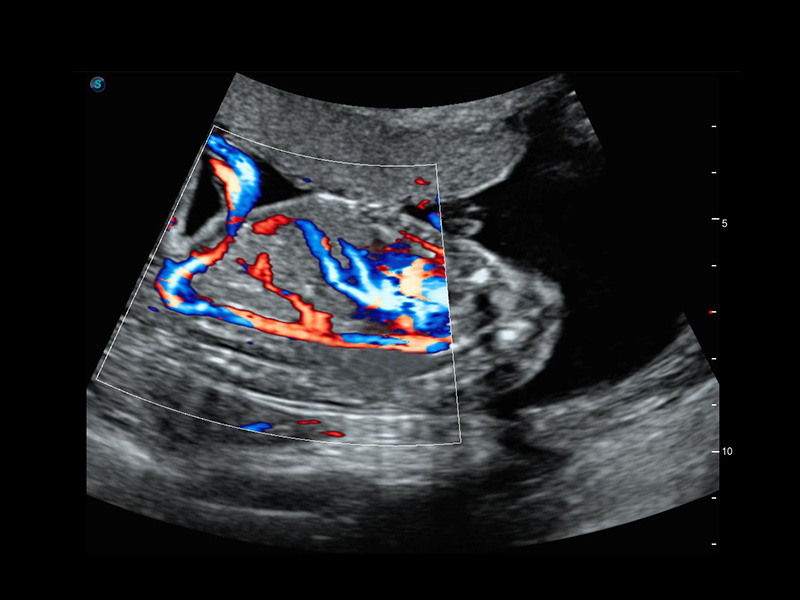

4D HyCoSy mit SPI

Die farbkodierte Hysterosalpingo-Kontrastsonografie (HyCoSy) ist eine proprietäre Funktion auf P60 Exp, die die Ankunftszeit von Kontrastmitteln in verschiedenen Teilen der Gebärmutter, der Eileiter und der Eierstöcke klar demonstrieren kann. Dadurch erhalten Kliniker starke und zuversichtliche Beweise, um die Tubenpatenz bei subfertilen Frauen zu untersuchen.

• Eileiter mit 4D HyCoSy

• Eileiter mit 4D HyCoSy mit SPI